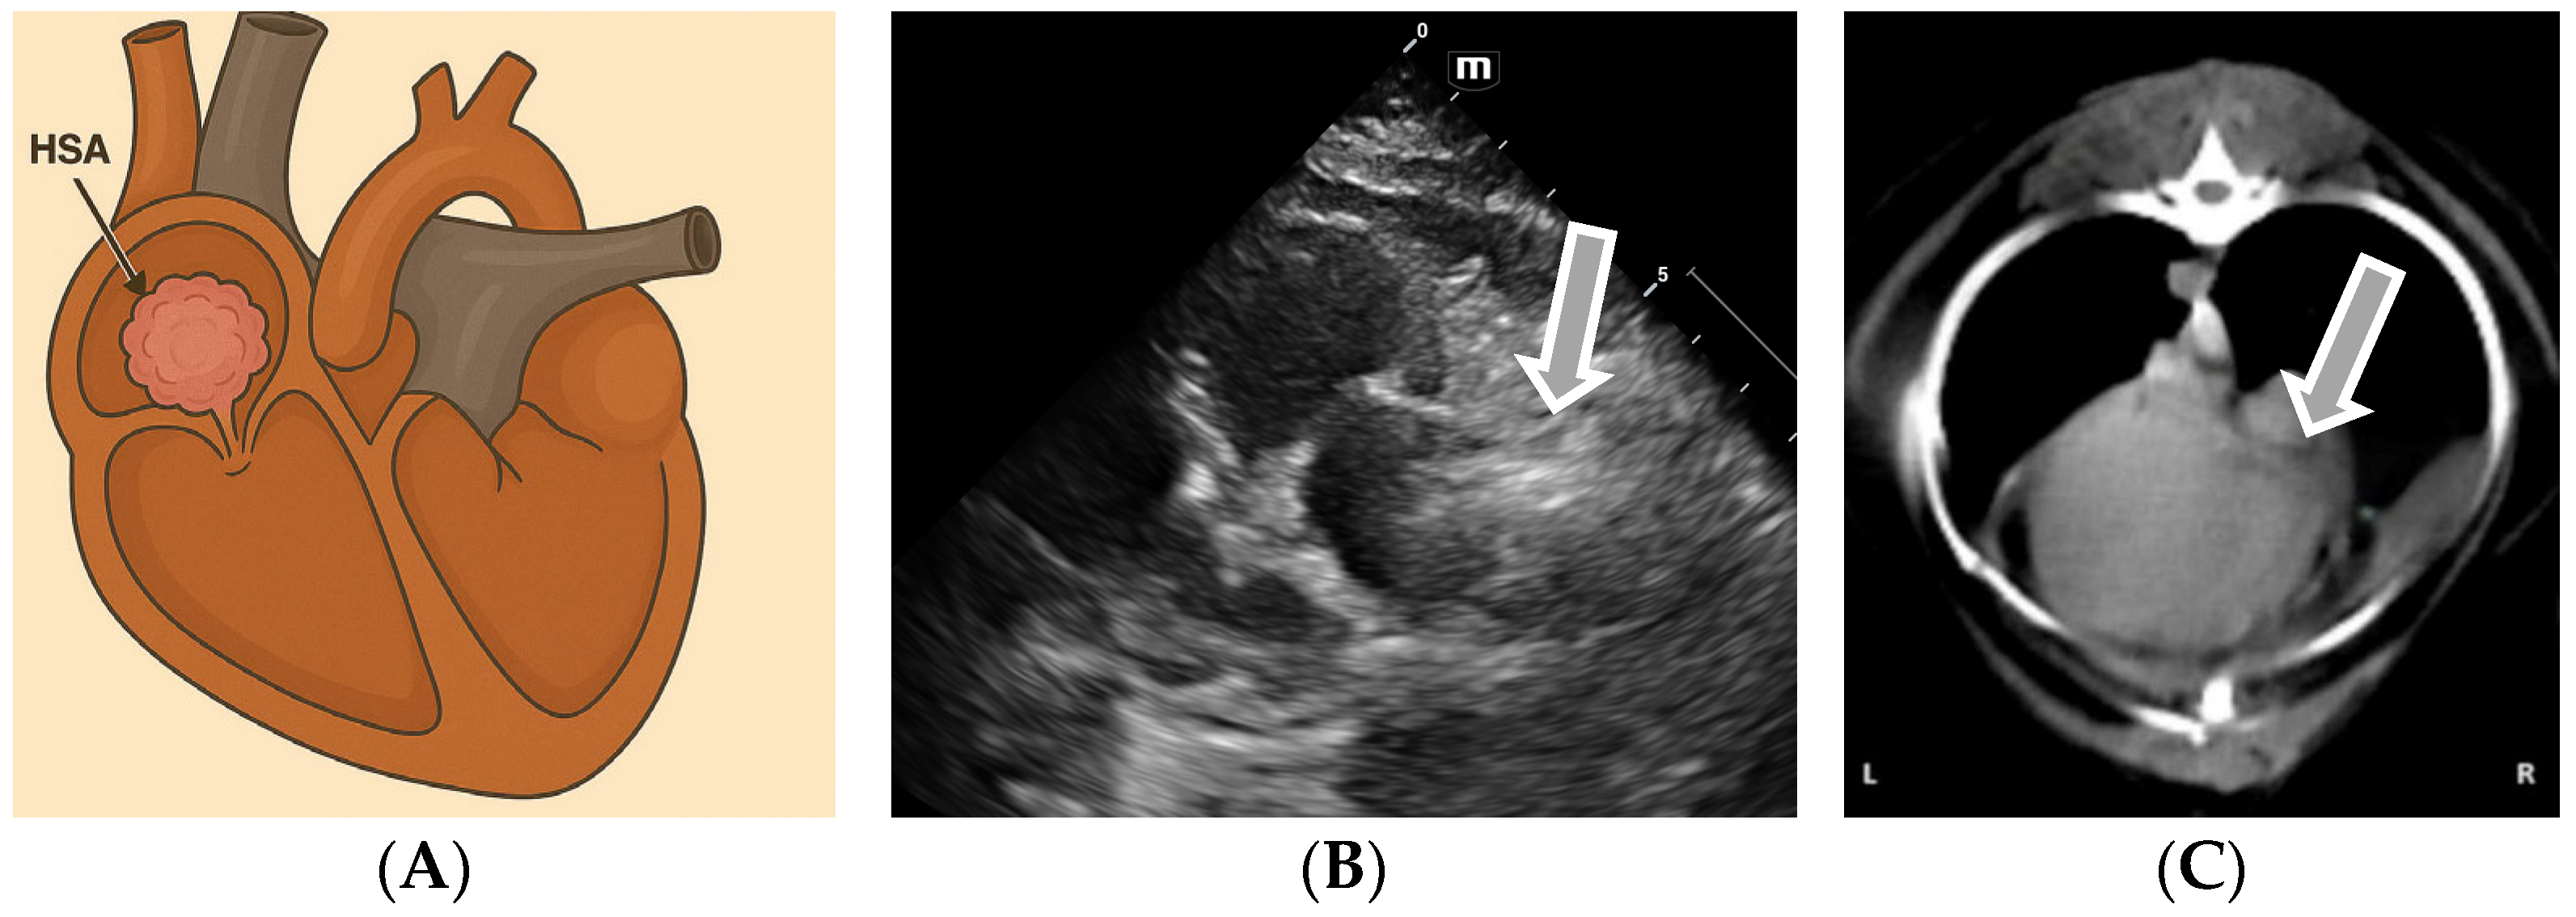

3.2. Echocardiographic Diagnosis of Atrial Hemangiosarcoma

| Hemangiosarcoma | Right atrium, pericardium | Lethargy, exertional syncope, jugular distension, ascites, collapse, dyspnea |